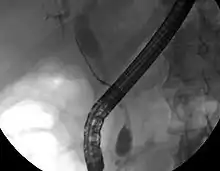

Imaging of the biliary tree

While abdominal imaging can be useful in the diagnosis of cholangiocarcinoma, direct imaging of the bile ducts is often necessary. Endoscopic retrograde cholangiopancreatography (ERCP), an endoscopic procedure performed by a gastroenterologist or specially trained surgeon, has been widely used for this purpose. Although ERCP is an invasive procedure with attendant risks, its advantages include the ability to obtain biopsies and to place stents or perform other interventions to relieve biliary obstruction.[12] Endoscopic ultrasound can also be performed at the time of ERCP and may increase the accuracy of the biopsy and yield information on lymph node invasion and operability.[54] As an alternative to ERCP, percutaneous transhepatic cholangiography (PTC) may be utilized. Magnetic resonance cholangiopancreatography (MRCP) is a non-invasive alternative to ERCP.[55][56][57] Some authors have suggested that MRCP should supplant ERCP in the diagnosis of biliary cancers, as it may more accurately define the tumor and avoids the risks of ERCP.[58][59][60]